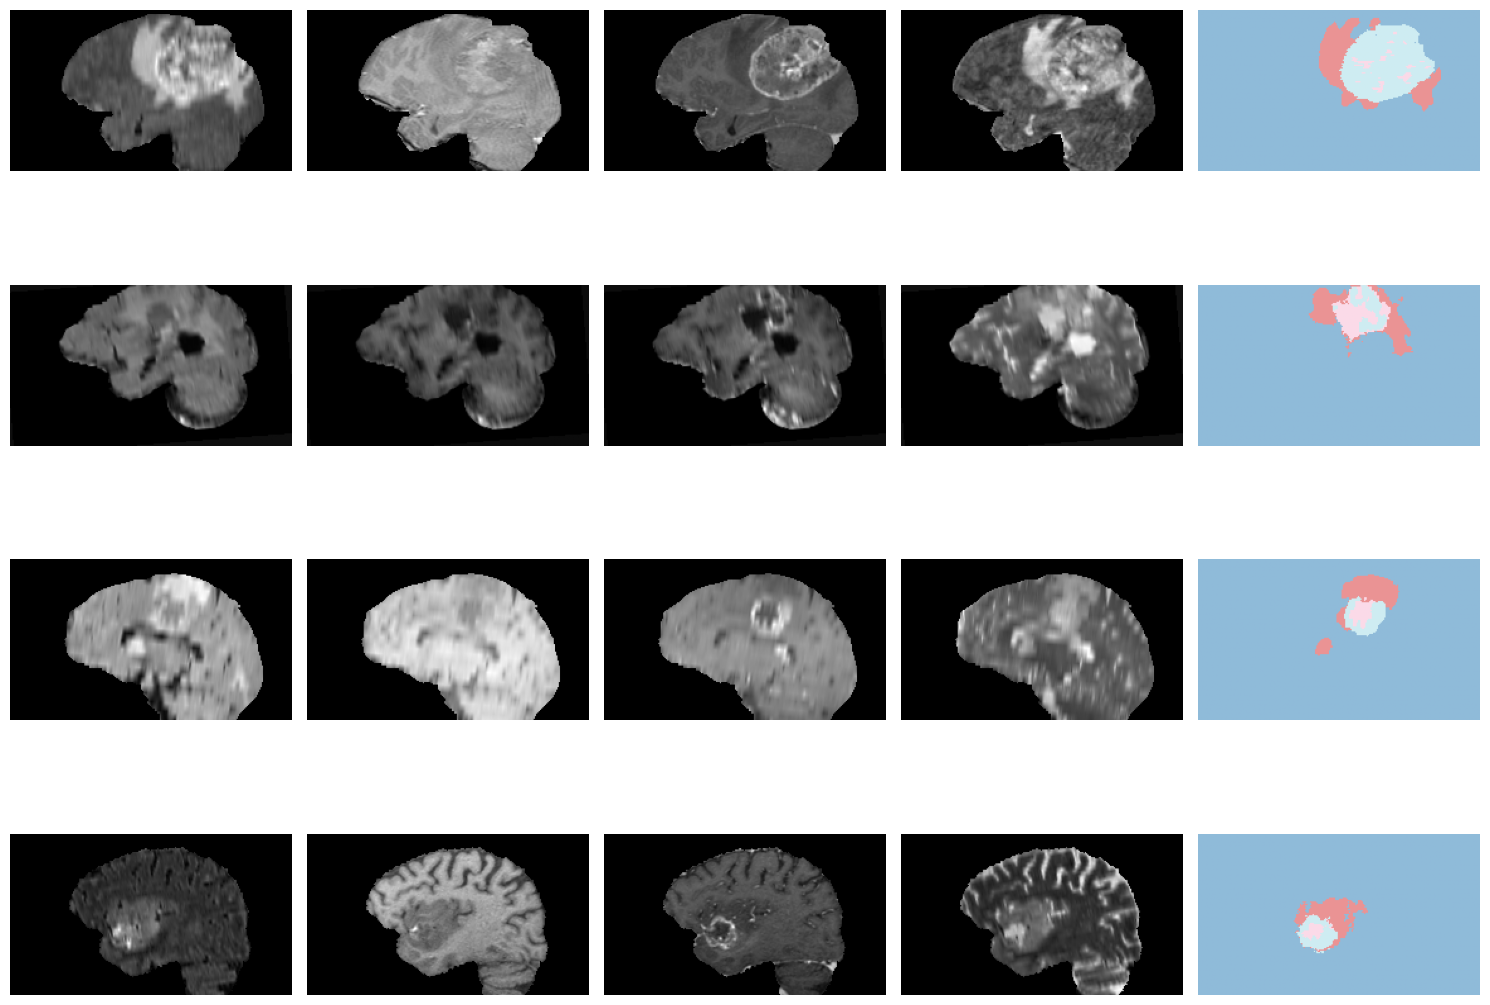

For the multi-class semantic segmentation task, we will use the brain tumors dataset from the Medical Segmentation Decathlon challenge (http://medicaldecathlon.com/). The data is collected from the Multimodal Brain Tumor Image Segmentation Benchmark Challenge (BraTS) dataset from 2016 and 2017. The task is to segment tumors into three different subregions (active tumor (AT), necrotic core (NCR), and peritumoral edematous/infiltrated tissue (ED)) from multimodal multisite MRI data (T1w, T1ce, T2w, and FLAIR). The challenge with this dataset is the brain tumors’ highly heterogeneous appearance and shape.

dls.show_batch(anatomical_plane=0)

learn.show_results(anatomical_plane=0, ds_idx=1)

learn.load('braintumor-weights');test_dl = learn.dls.test_dl(test_df[:10],with_labels=True)test_dl.show_batch(anatomical_plane=0, figsize=(10,10))

learn.show_results(anatomical_plane=0, dl=test_dl)